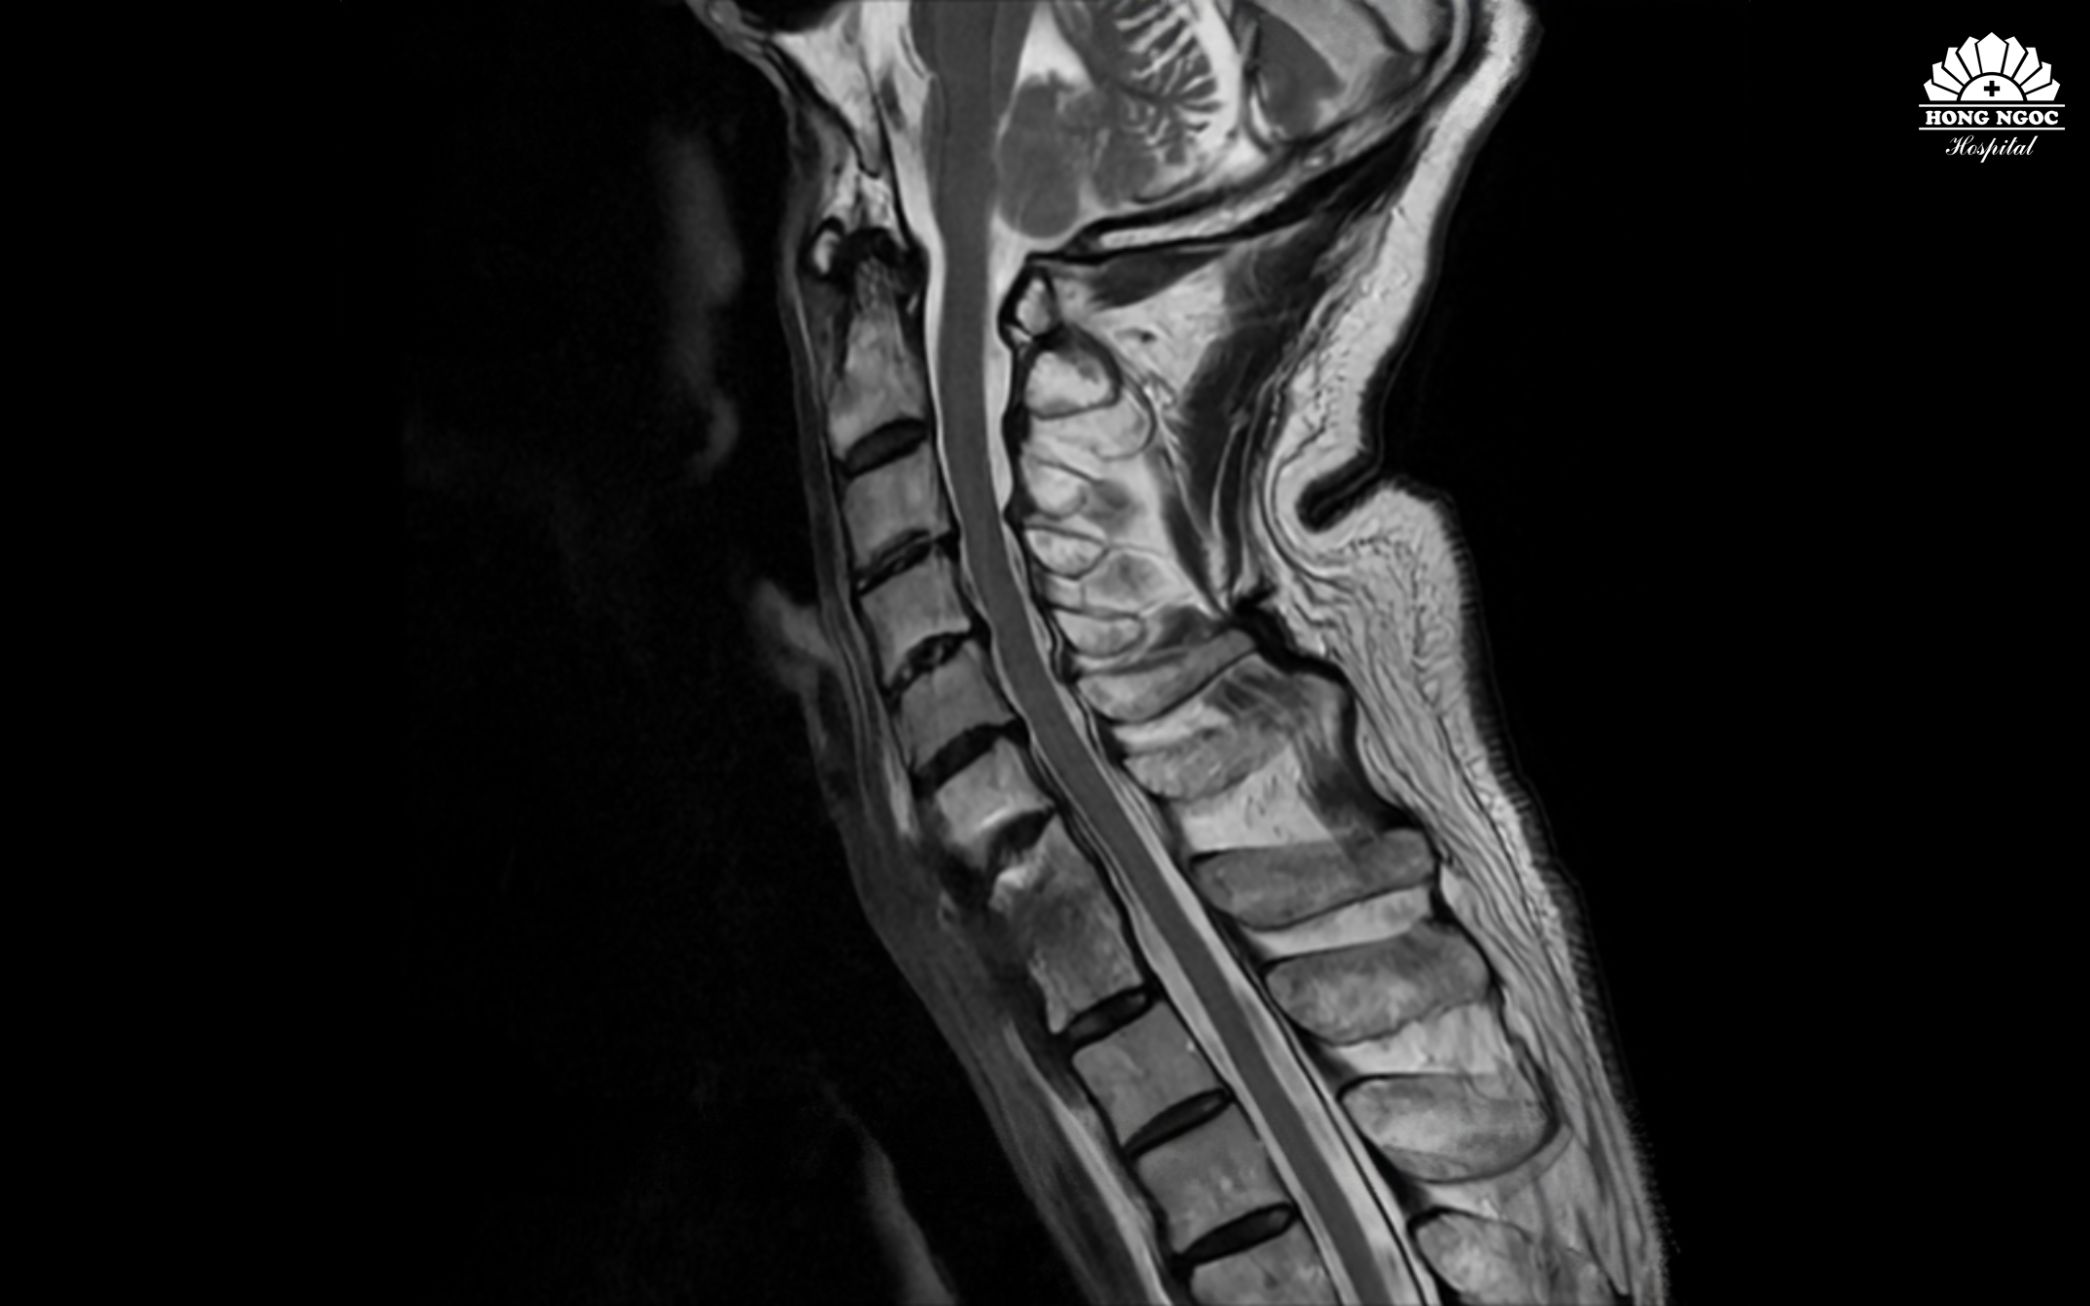

Dải xơ và ổ viêm đã được xử lý, lấy lại đường cong sinh lý, làm vững cột sống cổ

Dưới sự hỗ trợ của máy C-arm 3D tích hợp trí tuệ nhân tạo AI, sau hơn 2 giờ phẫu thuật PGS. Hà Kim Trung; THS.BSNT Nguyễn Quang Trung cùng toàn bộ ê - kíp đã thành công bóc tách phần xơ dính, xử lý ổ viêm, làm vững cột sống cổ. Hậu phẫu bệnh nhân tỉnh, tình trạng tê bì, đau mỏi cổ đã cải thiện, không yếu liệt chi, cổ có thể xoay, ngửa nhẹ nhàng.